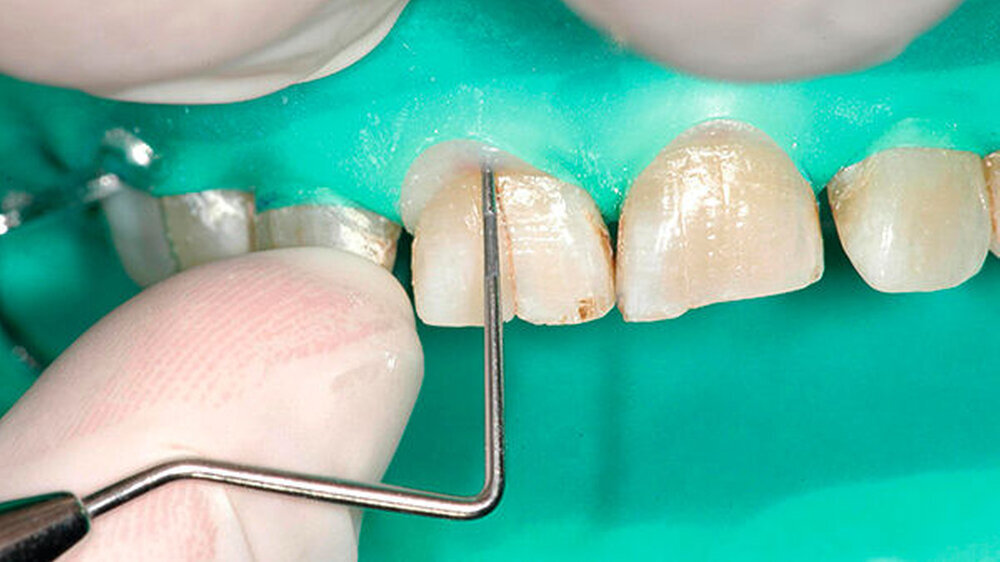

Während die palatinale Fläche unbeschädigt war, zeigte die bukkale Fläche eine vertikale Frakturlinie (Abbildung 3), die mit einem feinen diamantierten Schleifkörper erweitert wurde (Abbildung 4). Zusätzlich erfolgte die Entfernung des retrograden Wurzelkanalfüllmaterials. Beide Defekte wurden mit Biodentine (Septodont, Niederkassel) aufgefüllt (Abbildung 5).